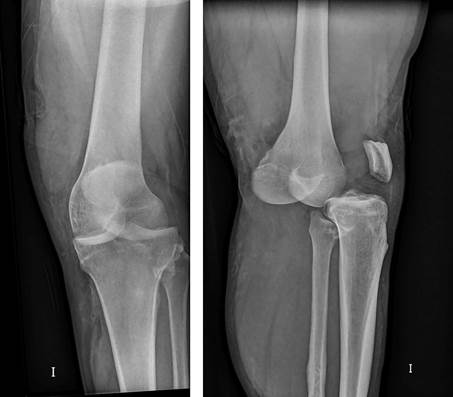

Hombre de 24 años, obeso, derivado de urgencias de AP por dolor, deformidad e impotencia funcional de la rodilla izquierda tras caída en bicicleta. No presenta heridas externas. En urgencias, tras asegurar la presencia de pulso distal y sensibilidad, procedemos a una valoración radiológica (figura 1), donde apreciamos una luxación anterior femorotibial. Bajo sedoanalgesia, reducimos la luxación y revaloramos la integridad neurovascular. Exploramos la integridad ligamentosa apreciando inestabilidad multidireccional: cajón posterior +++ y valgo +++. Inmovilizamos a 30º con férula posterior, comprobamos radiológicamente la reducción, sin apreciar fracturas, y derivamos al paciente a nuestro hospital de referencia, donde una angiotomografía computarizada (angio-TC) descarta lesiones vasculares, pero detecta una fractura de hundimiento de la cara anterior de la meseta tibial externa (figura 2), confirmada posteriormente con una resonancia magnética (RM), que además determina las lesiones musculoesqueléticas asociadas a la luxación: rotura de ligamento cruzado anterior (LCA), rotura parcial del ligamento cruzado posterior (LCP), rotura del ligamento colateral medial (LCM), rotura del tendón semimembranoso y tendones de la pata de ganso, y rotura del menisco interno. Se inmoviliza con fijador externo (figura 3) y se interviene 18 días más tarde, iniciando la rehabilitación al día siguiente, inicialmente con movilización suave, carga progresiva desde el primer mes, bicicleta sin resistencia a partir del segundo mes y piscina. Como secuela, 6 meses después de la lesión, presenta un leve bostezo en valgo que no le impide caminar. Dos años más tarde, hace vida normal, incluyendo laboral y deportiva.